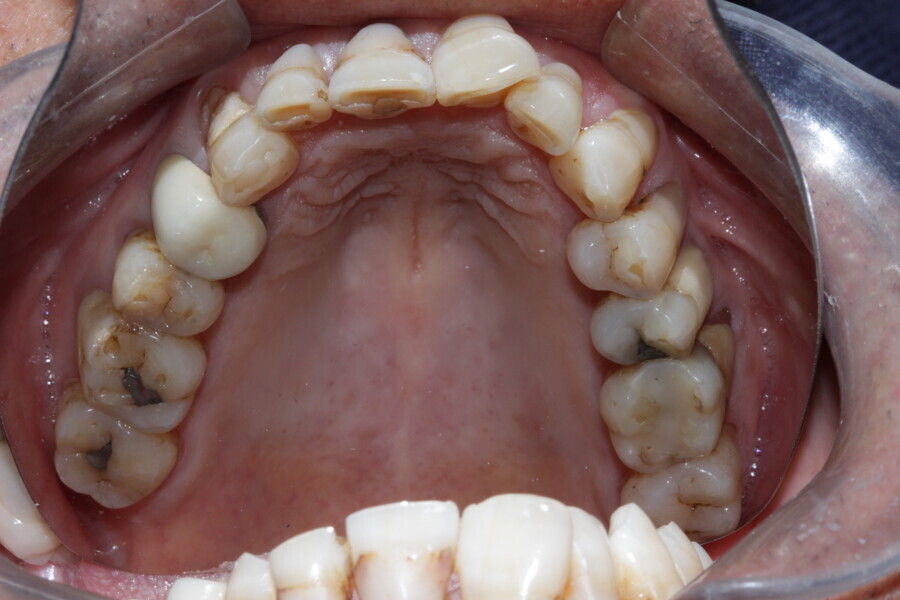

Figure 6 Maxillary occlusal view before treatment